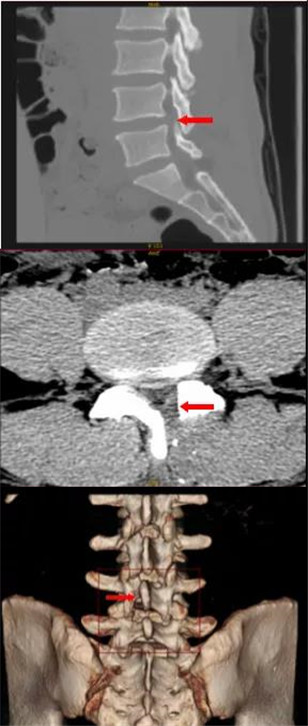

唐先生慕名来到桂林医学院附属医院脊柱外科就诊,住院后经过系统检查明确诊断为「腰椎管狭窄伴腰椎间盘突出」。

术前MRI提示腰椎管狭窄伴腰椎间盘突出

术后腰 4/5 椎间盘突出术后改变